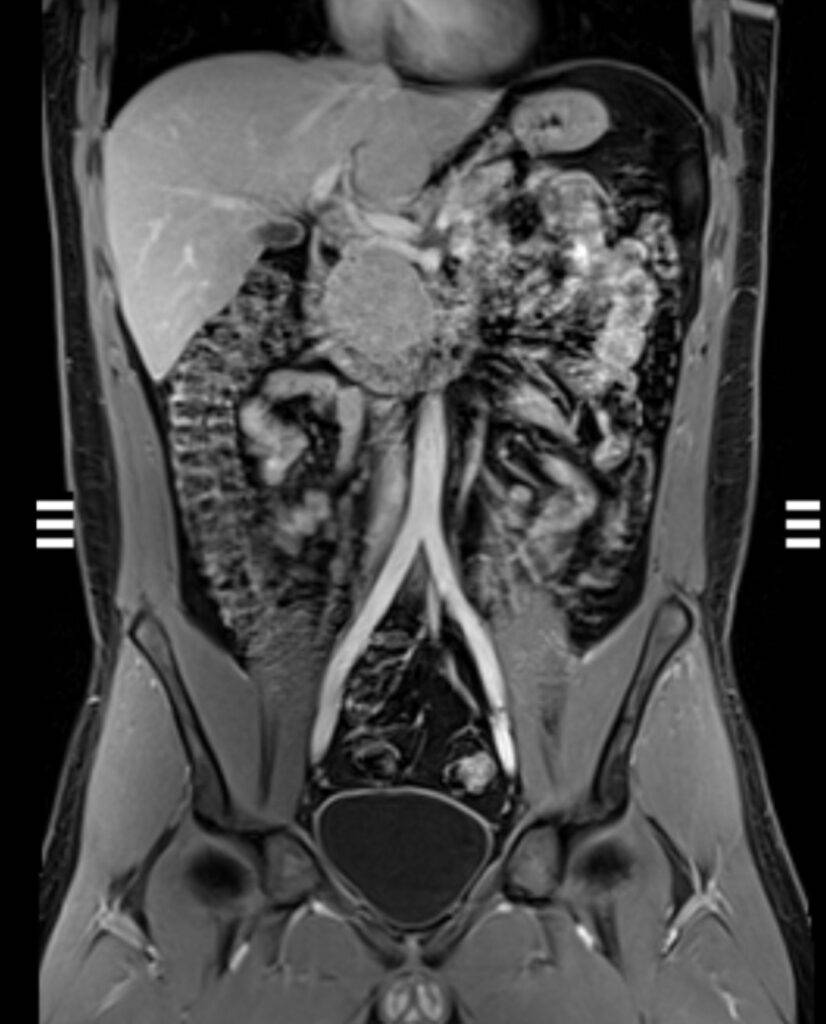

Was kann man auf einer MRT des Abdomens sehen?

Auf einer MRT-Aufnahme sind insbesondere die Organe im Bauchraum sichtbar, da Weichteile in einer MRT sehr gut abgebildet werden können.

Zu sehen und später im weiteren Verlauf beurteilbar sind:

- Leber, Gallengängen, Bauchspeicheldrüse, Nieren und Nebennieren mit Harnleiter, Milz, Becken

Durch die detailreichen Abbildungen können Veränderungen der Organe festgestellt werden, die auf bestimmte Krankheiten schließen lassen – so können beispielsweise Entzündungen oder Gewebsveränderungen im Bauchraum festgestellt werden.

Es kann zwischen gut- und bösartigen Tumoren unterschieden werden. Dies ermöglicht eine genaue Diagnose, woraufhin ein schnelles und geeignetes Therapieverfahren angesetzt werden kann.

Auch bei diffusen und nicht lokalisierbaren Schmerzen im Bauchraum kann eine MRT- Untersuchung Klarheit schaffen.